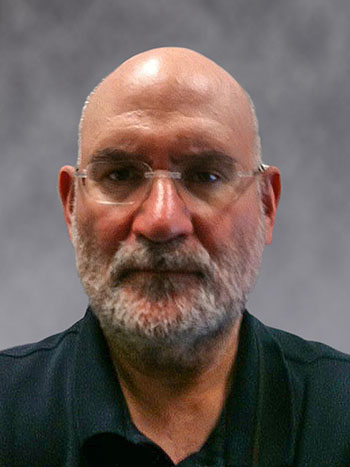

fMRI of viewing and matching facial expressions

BOLD fMRI activation, depicted in color, of left anterior insula (MNI plane z = 8 mm) in a single subject by a contrast between viewing and matching faces with negative emotion (angry, sad, scared) versus happy faces. The voxelwise threshold is p < 0.001, and colored voxels survive false discovery rate correction to p < 0.05. The activated voxels in color are overlaid on the subject's own 3D-TFE image displayed in grayscale, after transforming the data to MNI space. The fMRI pulse sequence was a single shot FFE echo planar acquisition using MultiBand SENSE factor 6, dS SENSE factor 1, isotropic voxel size 2.4 mm, 60 transverse slices, TR 950 ms, TE 30 ms, flip angle 52 degrees, 517 dynamic scans, total scan duration 8:21 minutes. Image provided by James M. Bjork, PhD, Associate Professor of Psychiatry at VCU.